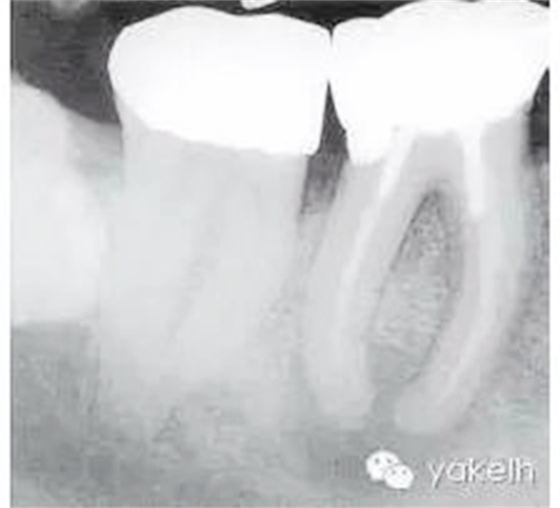

根尖X線片顯示什么(圖5.1.1)?

圖5.1.146術(shù)前X線片,顯示金屬冠修復(fù),每個(gè)牙根內(nèi)均有金屬樁,根管充填物均短于放射學(xué)根尖且有根尖周透射影。

金屬冠修復(fù)。

近遠(yuǎn)中牙根內(nèi)均有金屬樁。

在近中根內(nèi),樁的尖端向根管側(cè)壁偏移。

近遠(yuǎn)中牙根均有中度彎曲。

近遠(yuǎn)中根管充填物均短于放射學(xué)根尖。

近遠(yuǎn)中根尖周均有明顯的透射影。

右下頜第三磨牙(48)緊靠右下頜第二磨牙(47)遠(yuǎn)中。